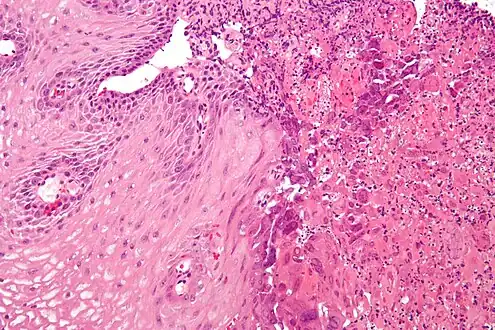

Microscopic Slide of Eosinophilic Esophagitis

Eosinophilic esophagitis

Eosinophilic esophagitis is caused by a high concentration of eosinophils in the esophagus. The presence of eosinophils in the esophagus may be due to an allergen and is often correlated with GERD. The direction of cause and effect between inflammation and acid reflux is poorly established, with recent studies (in 2016) hinting that reflux does not cause inflammation.[6] This esophagitis can be triggered by allergies to food or to inhaled allergens. This type is still poorly understood.